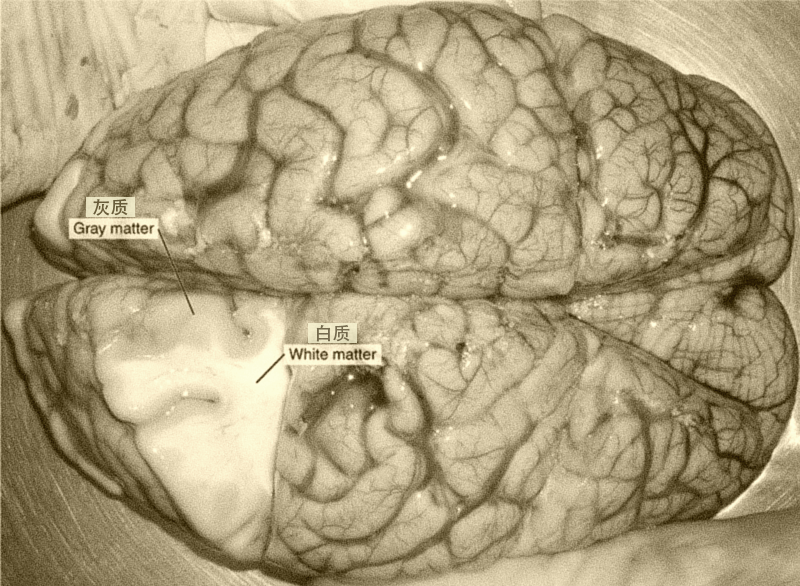

SCP-7380的X射线成像,在